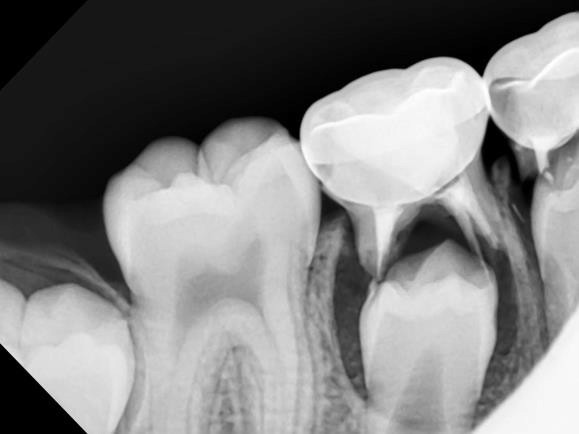

Dental sealants are thin, plastic coatings that seal over the narrow grooves found on the chewing surfaces of back teeth (molars and premolars).

When placed perfectly on these deep pits, sealants can prevent a significant amount of tooth decay (cavities) by protecting sensitive tooth surfaces from acid that causes cavities.

Sealants are not generally placed on baby teeth but on the tooth enamel of permanent teeth (“adult” teeth).

Dental sealants function much like sealing cracks in a driveway or on the sidewalk. The grooves in the chewing surfaces of back teeth are sealed so that food particles and bacteria will not settle within the fissures, causing cavities.

Application of sealants may be appropriate for some pediatric dental patients to prevent tooth decay in kids. However, they are not a substitute for brushing, flossing, and a healthy diet.

How are sealants applied to teeth?

Sealant placement is a relatively easy process.

First, the teeth are cleaned of plaque or food particles and then thoroughly examined for tooth decay.

Each tooth is dried and surrounded by absorbent material so it remains dry throughout the procedure.

The tooth is cleaned with a mild etchant (acid etch solution) to roughen the tooth surface and encourage bonding of the sealant material.

The etchant is rinsed and the teeth are dried again.

Depending on your material of choice, a thin layer of bonding agent may be used prior to the placement of the very viscous sealant material.

The sealant is painted directly onto the chewing surface of each tooth.

Finally, a curing light may be used to harden the dental sealant.

The teeth must be nicely isolated so no contaminants, such as saliva, affect the bond. Ozone gas can be applied to ensure bacteria on or around the tooth is reduced or eliminated prior to sealing.

If a small cavity is detected, air abrasion or a dental laser or drill can be used to clean out the infection prior to any material placement.